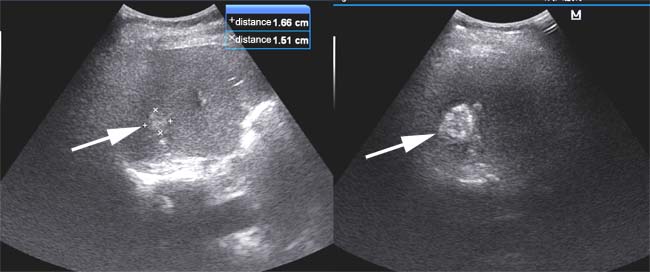

From Jan 2012 to Jan 2014, 62 CRLM patients underwent clinical treatment of CRLM at our department. Firstly, the liver biopsy was carried out before the treatment, and then the type of pathological samples were defined by two sophiscated pathology doctors (Figure 1). After the diagnosis of CRLM, MWA was conducted in 45.2% (28/62) of CRLM patients as described above and shown in Figure 2. Patient demographics are shown in Table 1. 34 cases of patients underwent hepatectomy. In the patient cohort, 46.8% (29/62) of all patients were female, and the median age was 60 years. Nearly all patients received either preoperative and/or postoperative chemotherapy. In addition, single tumor account for 64.5% of all tumors, and showed no differences from multiple tumors in both groups (p = 0.973). The pathological type of most tumors was low/mild differentiated in MWA (85.7%) and resection (82.4%) group. Most importantly, there was no significant difference between treatment and control cohort in tumor size (p = 0.487), liver metastasis time point (p = 0.368), Child-Pugh (p = 0.652) or pathological type (p = 0.884). These results suggested that the baselines in both group has no differences.

Figure 2: Procedure of MWA using ultrasound imaging. The white arrow indicated the potential lesions in the liver. At the same time, we calculated the diameter of tumors as shown in the right and upper part of images.